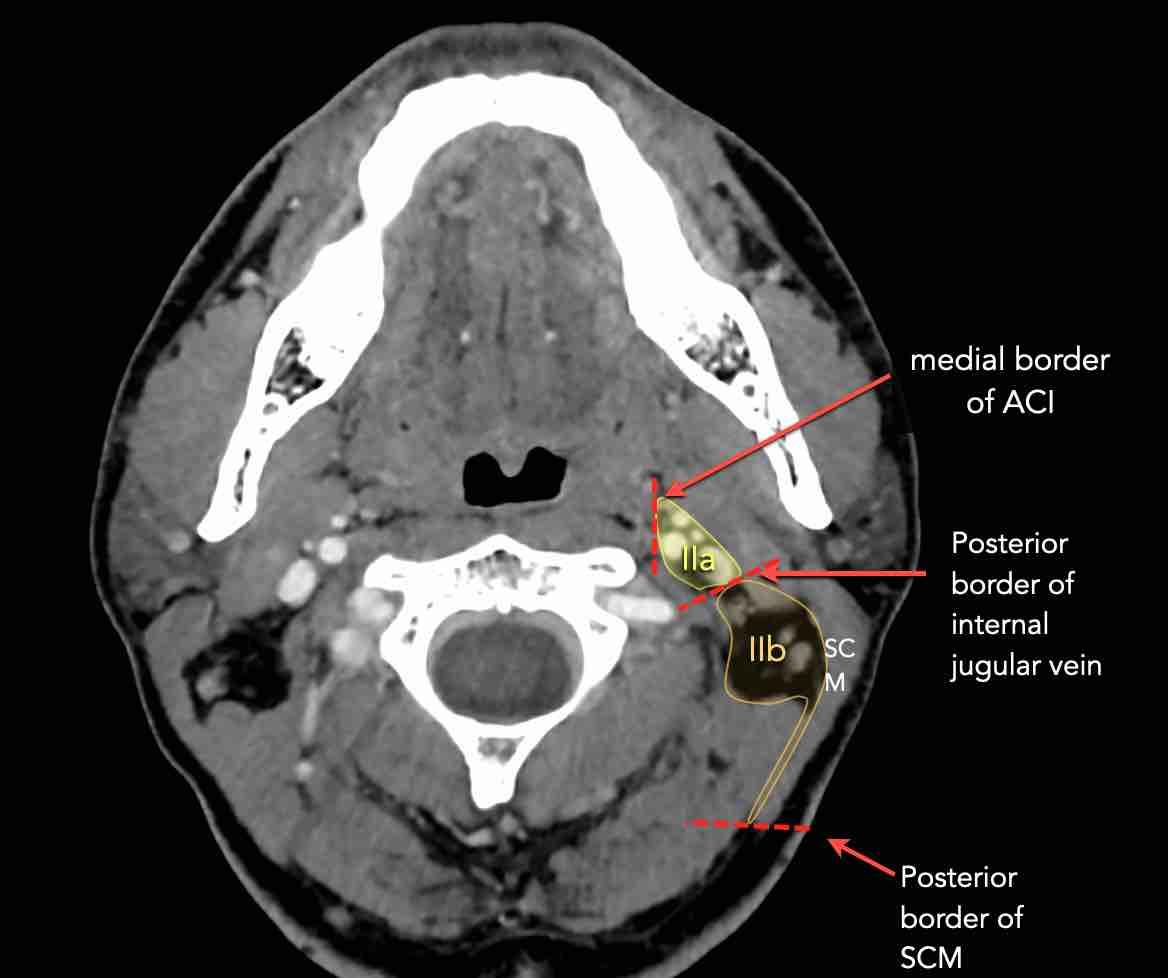

Tầng II có thể được chia thành tầng IIa và tầng IIb bằng cách vẽ một đường tại bờ sau của tĩnh mạch cảnh trong.

Các hạch bạch huyết ở tầng IIa và IIb có nguy cơ chứa di căn từ các ung thư hốc mũi và khoang miệng, vòm hầu, hầu miệng, hạ hầu, thanh quản và các tuyến nước bọt lớn.

Tầng IIb thường liên quan hơn đến các khối u nguyên phát ở hầu miệng hoặc vòm hầu, và ít thường xuyên hơn với các khối u ở khoang miệng, thanh quản hoặc hạ hầu [1].